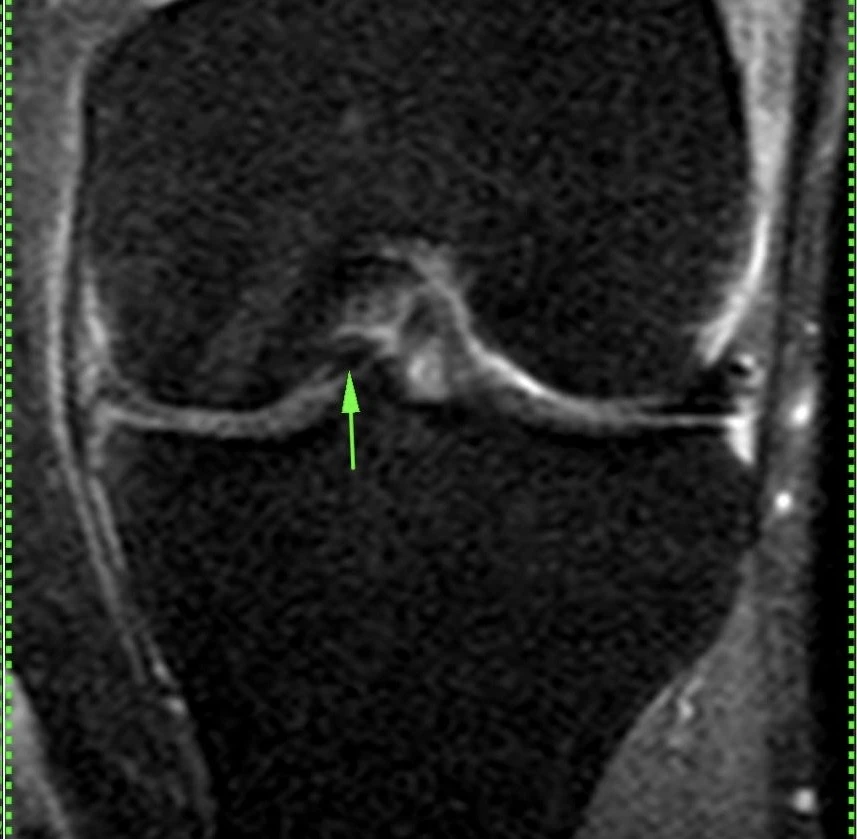

Обширная, ветвистая венозная мальформация (ранее известная, да и до сих пор тоже, как гемангиома) мягких тканей области коленного сустава.

Картина типичная, дифференциальная диагностика не требуется.

Представляет собой скопление аномальных, расширенных, извитых венозных сосудов, стенка которых гистологически не отличается от стенок обычных вен. Хорошо видны связи мальформации с обычными венами. Внутри некоторых из полостей видны выпадение сигнала, которые являются флеболитами (кальцинированными внутрисосудистыми тромбами).

Кстати, может никак не проявляться клинически, будучи даже таких больших размеров.